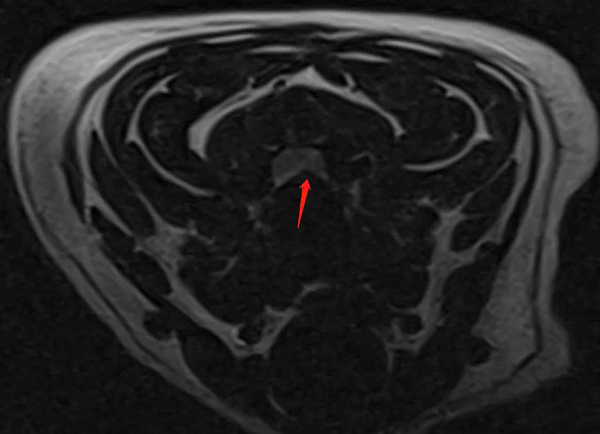

Chẩn đoán hình ảnh

- MRI: Xác định đĩa đệm C3 – C4 thoát vị, chèn ép tủy sống cổ, gây triệu chứng thần kinh.

MRI xác nhận thoát vị đĩa đệm C3 – C4 ra phía sau, biến dạng tủy sống, có tín hiệu T2W cao quanh vùng chèn ép.

Các đĩa đệm cổ khác cũng xuất hiện dấu hiệu mất nước ở nhiều mức độ.